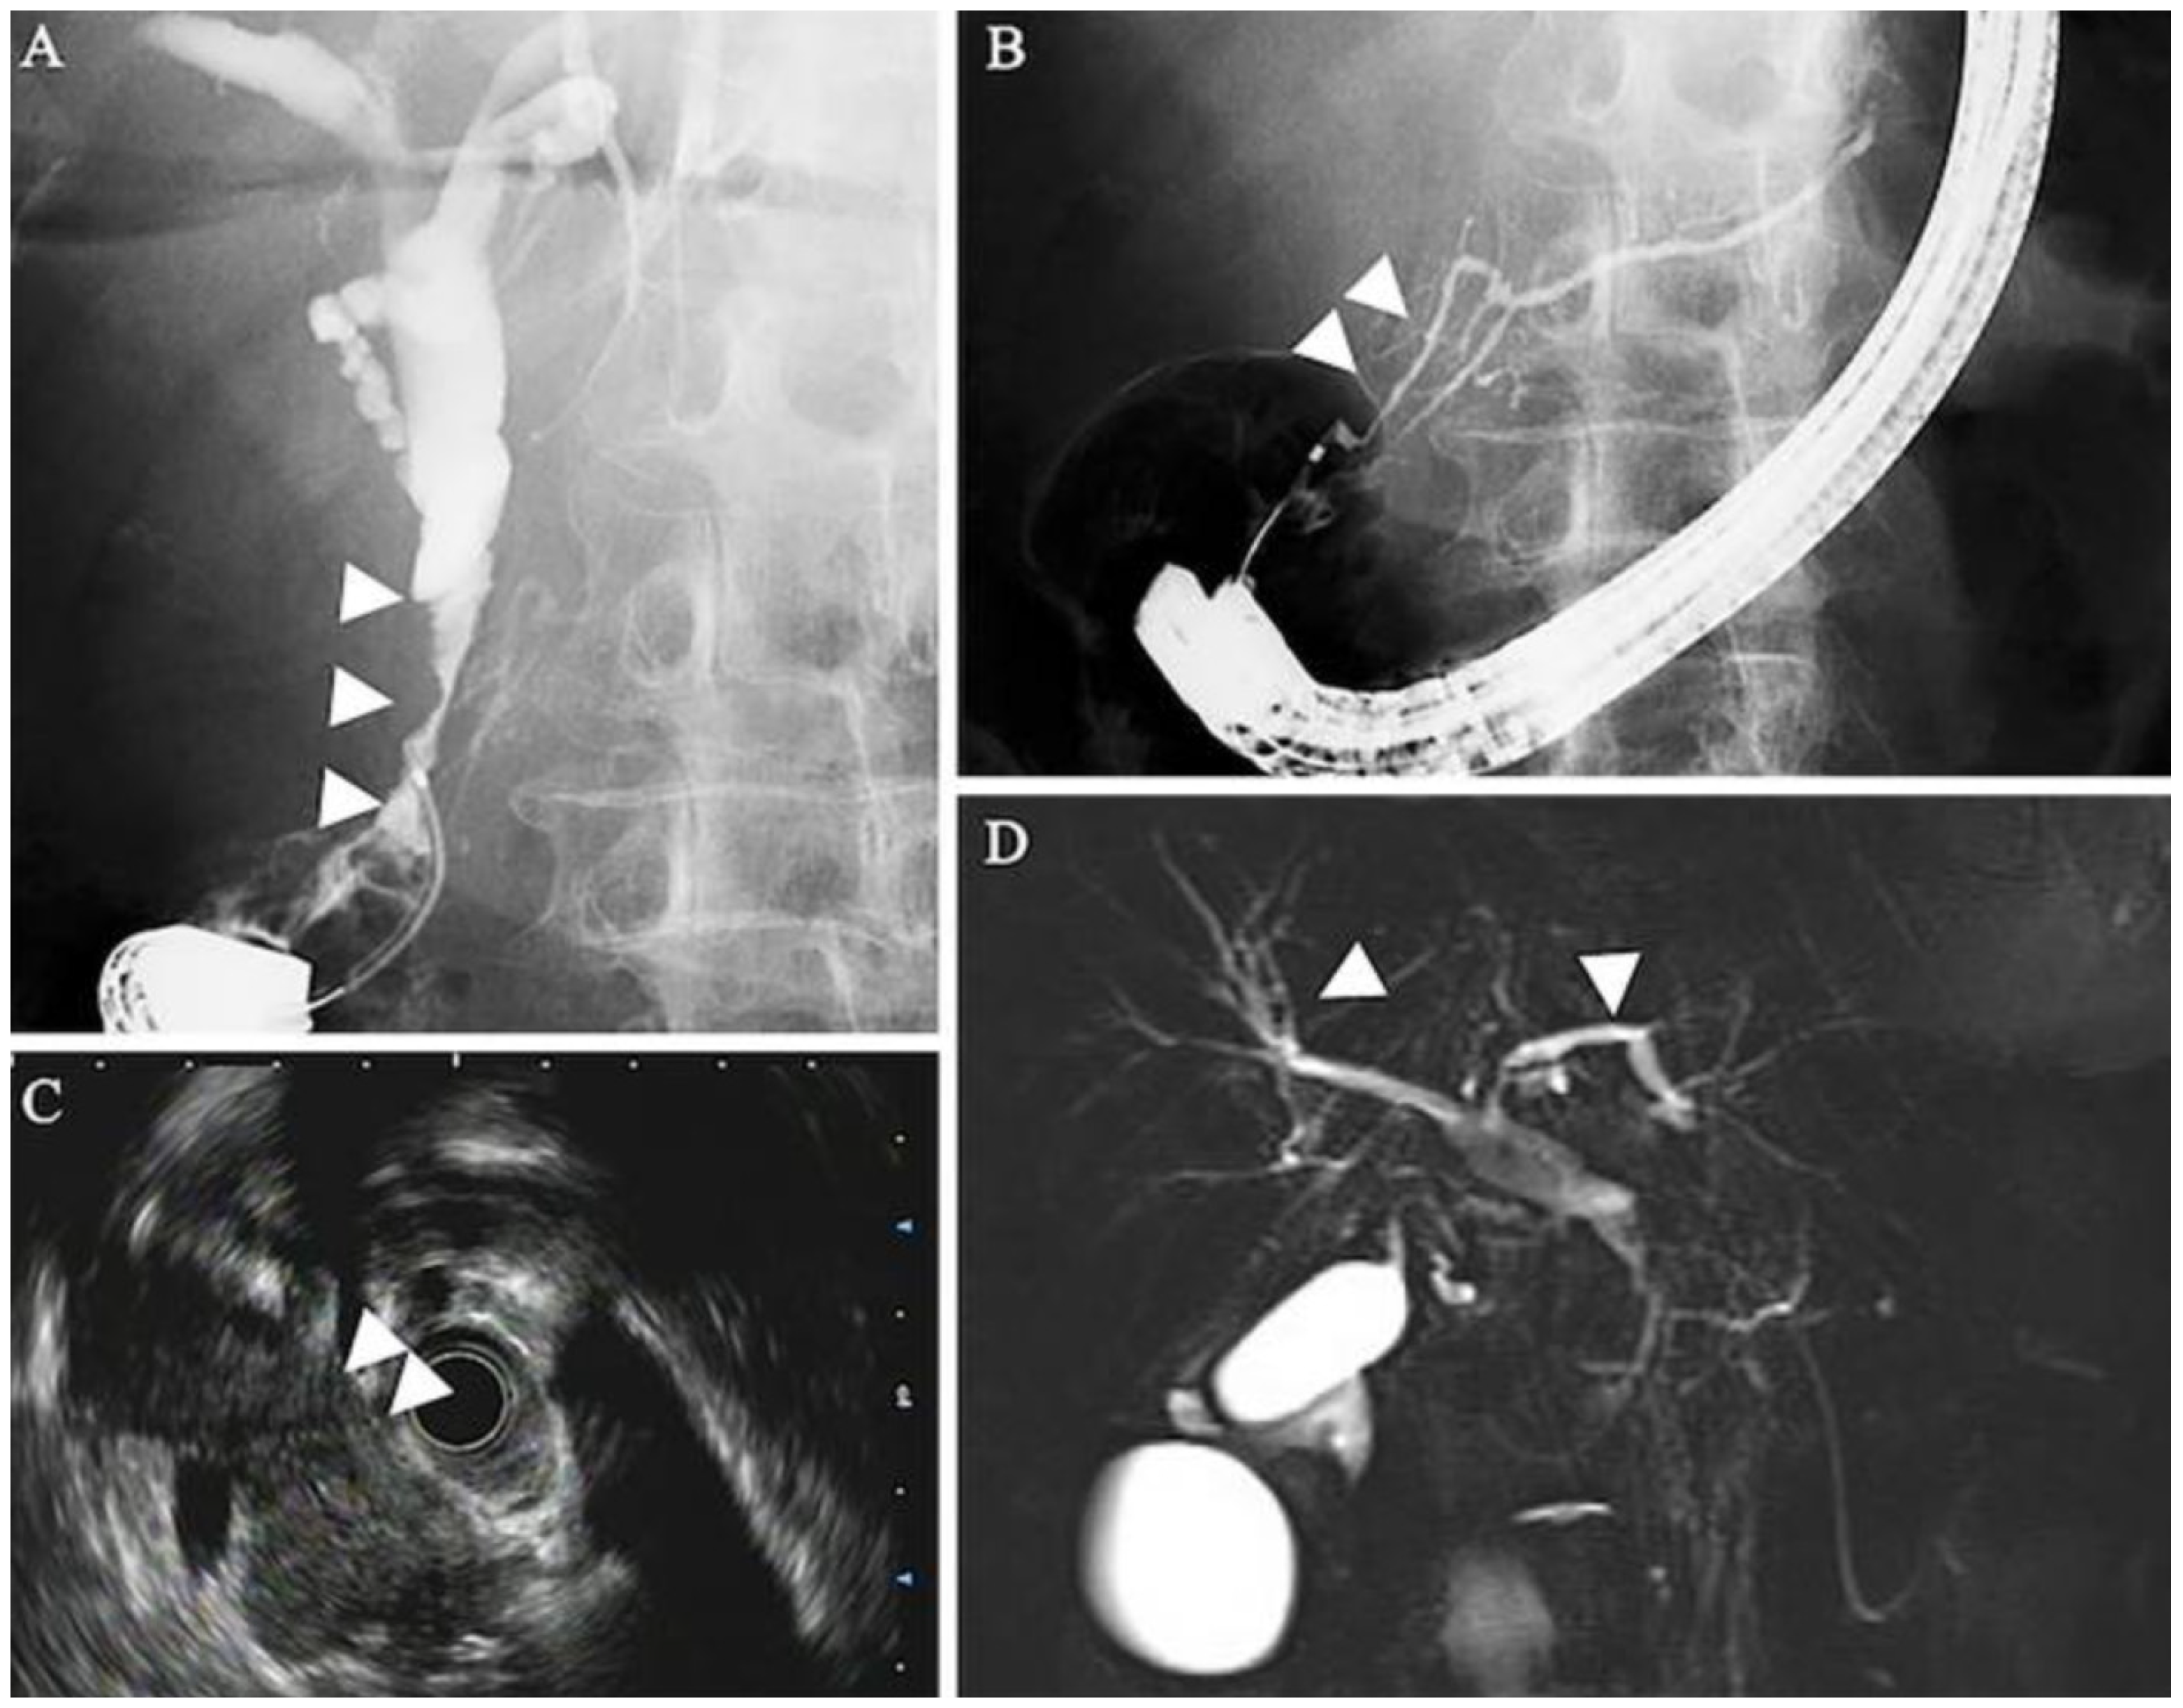

5.1. Radiographic Findings

- Rehnitz, C.; Klauss, M.; Singer, R.; Ehehalt, R.; Werner, J.; Büchler, M.W.; Kauczor, H.-U.; Grenacher, L. Morphologic patterns of autoimmune pancreatitis in CT and MRI. Pancreatology 2011, 11, 240–251. [Google Scholar] [CrossRef]

- Lee, S.; Kim, J.H.; Kim, S.Y.; Byun, J.H.; Kim, H.J.; Kim, M.-H.; Lee, M.-G.; Lee, S.S. Comparison of diagnostic performance between CT and MRI in differentiating non-diffuse-type autoimmune pancreatitis from pancreatic ductal adenocarcinoma. Eur. Radiol. 2018, 28, 5267–5274. [Google Scholar] [CrossRef]

- O’Reilly, D.A.; Malde, D.J.; Duncan, T.; Rao, M.; Filobbos, R. Review of the diagnosis, classification and management of autoimmune pancreatitis. World J. Gastrointest. Pathophysiol. 2014, 5, 71–81. [Google Scholar] [CrossRef]